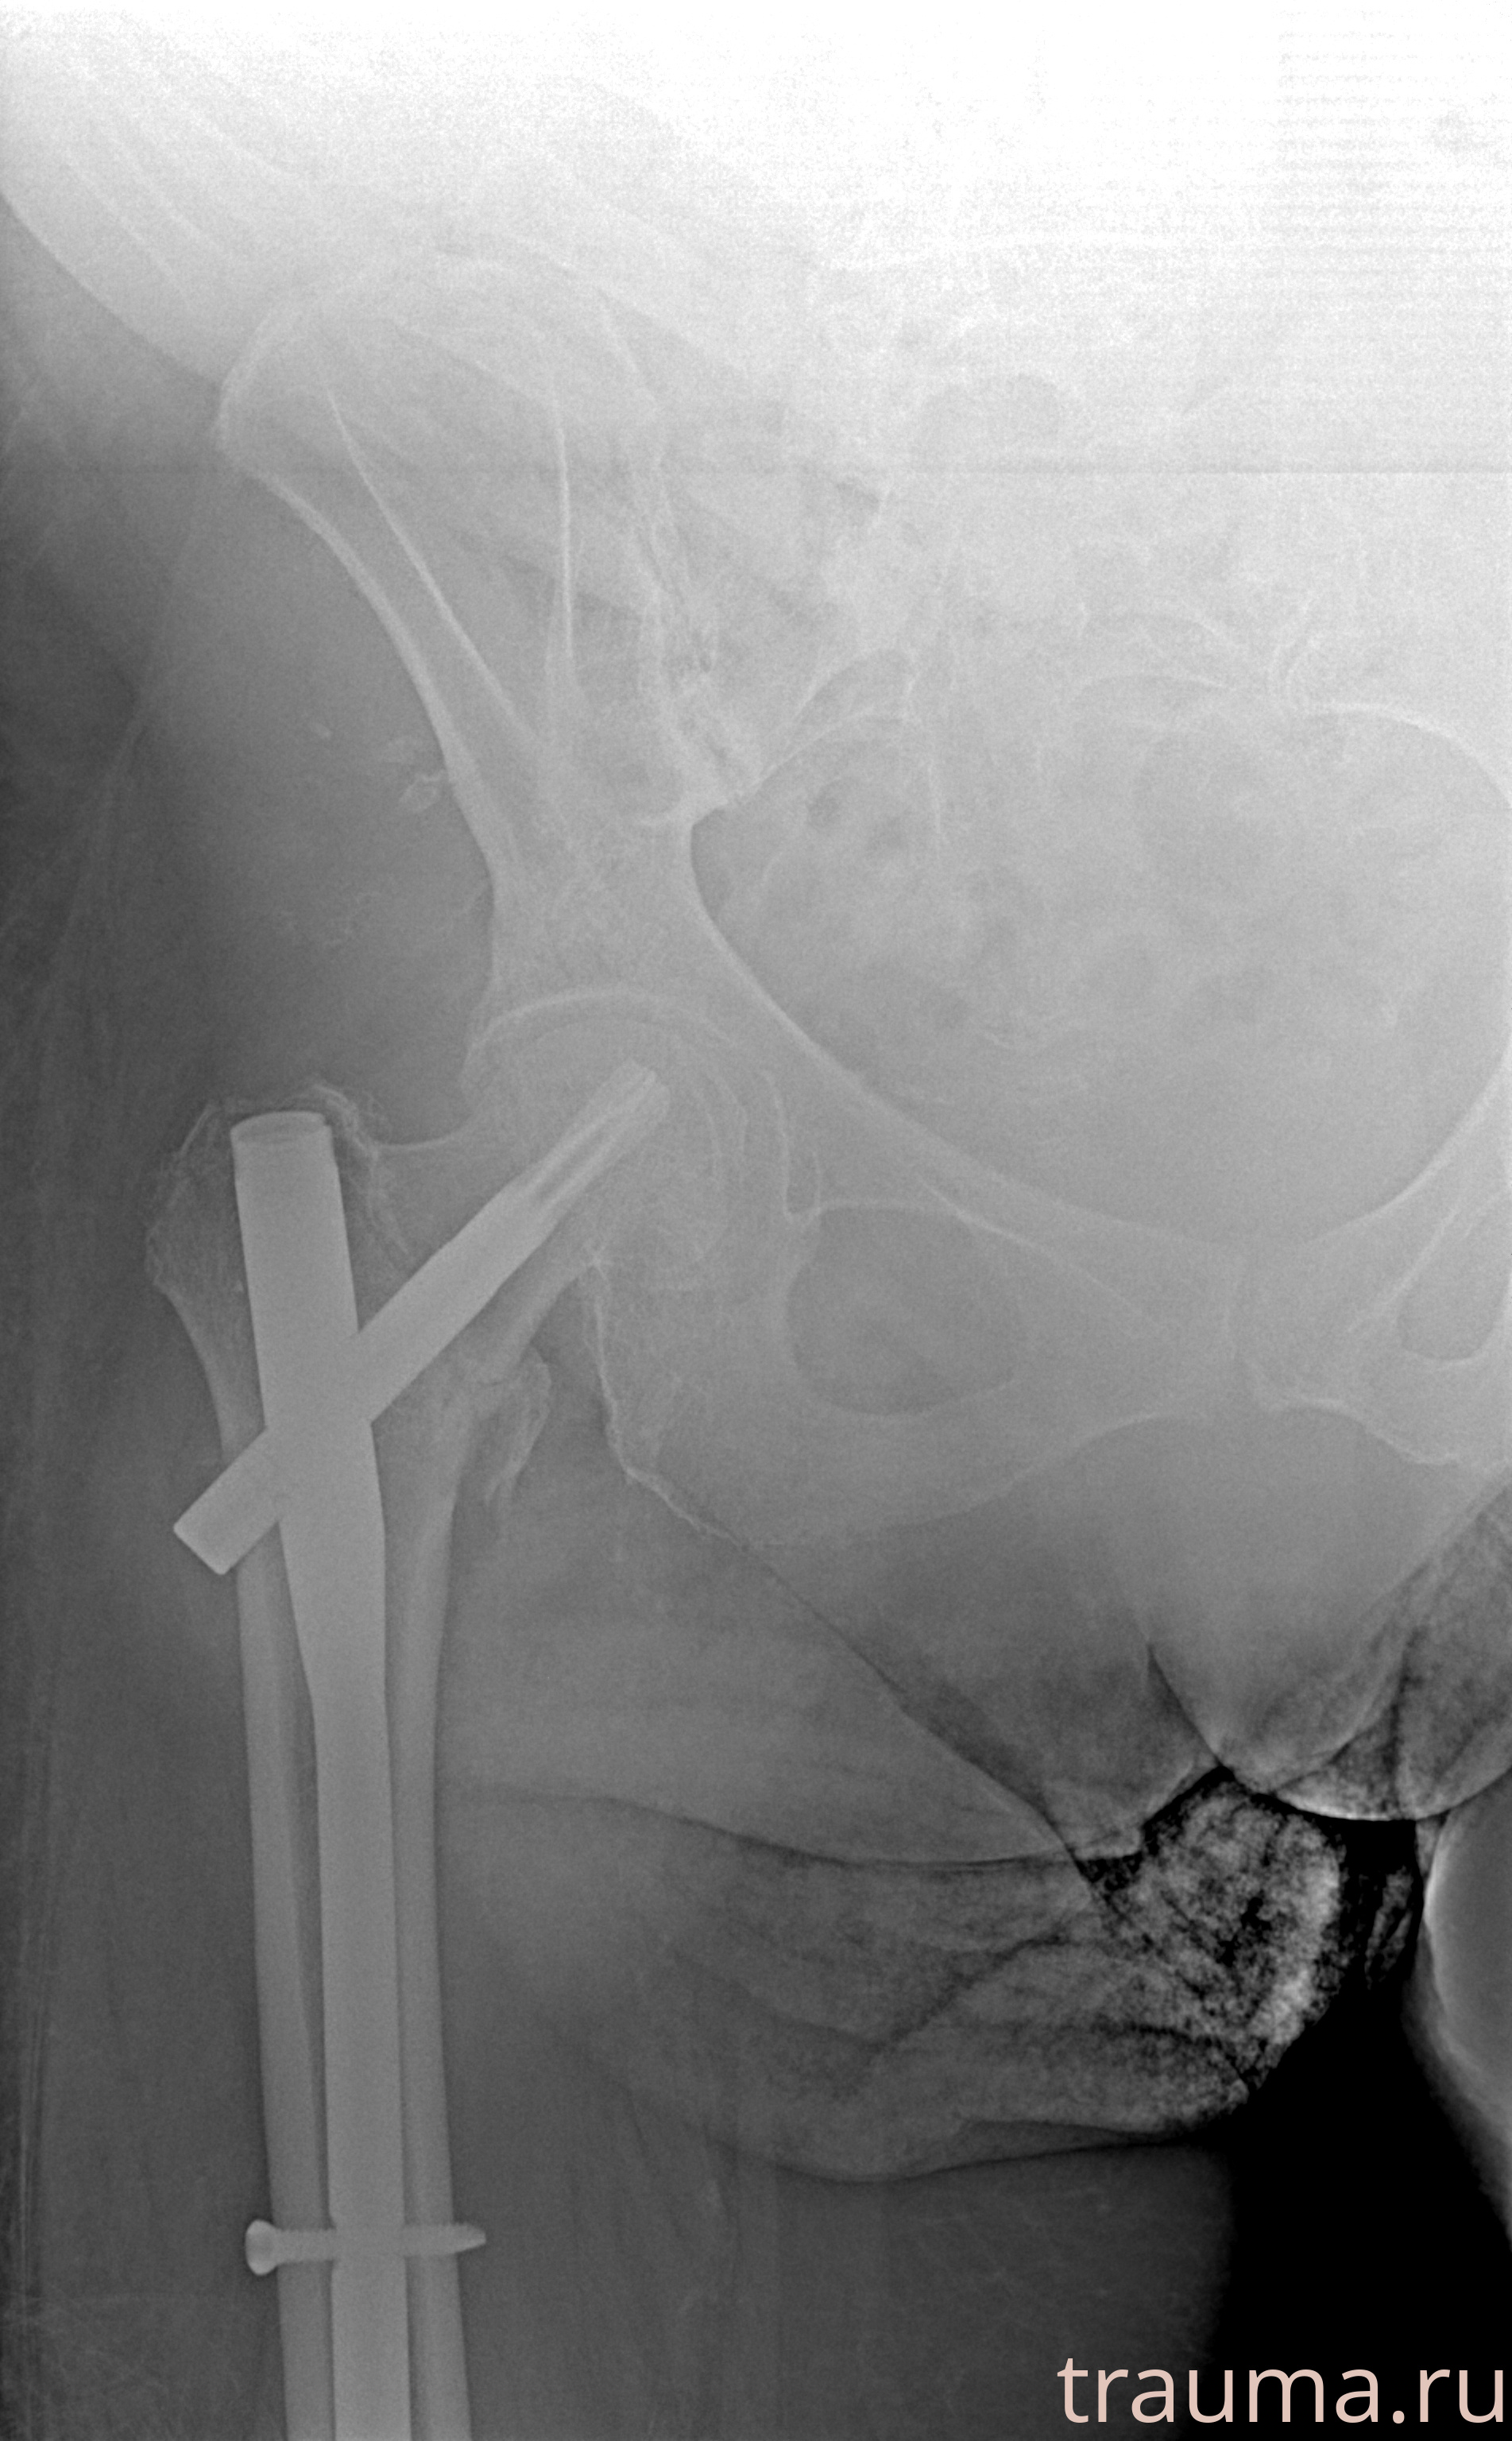

Рентгенограммы

Рентген на дому: по вашему адресу приезжает врач-рентгенолог, травматолог-ортопед с мобильным рентгеновским аппаратом, проводит диагностику травмы или заболевания, делает необходимые рентгенограммы, дает рекомендации по дальнейшему лечению. Получить качественные снимки в домашних условиях возможно благодаря уникальной методике, разработанной МосРентген Центром для института  Склифосовского